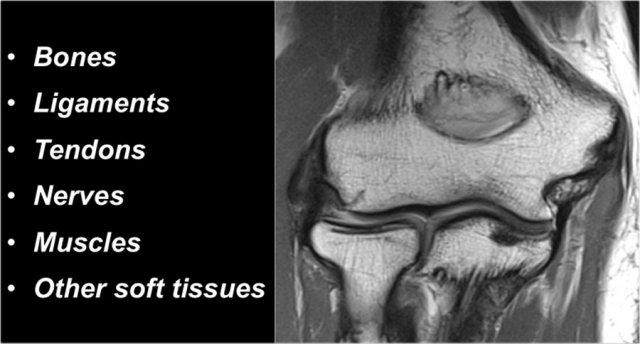

Khi nghiên cứu giải phẫu khuỷu tay, nên sử dụng phương pháp từ trong ra ngoài.

Đầu tiên hãy nghiên cứu các xương, sau đó tiếp tục với các dây chằng và gân, rồi đến các cấu trúc xung quanh.